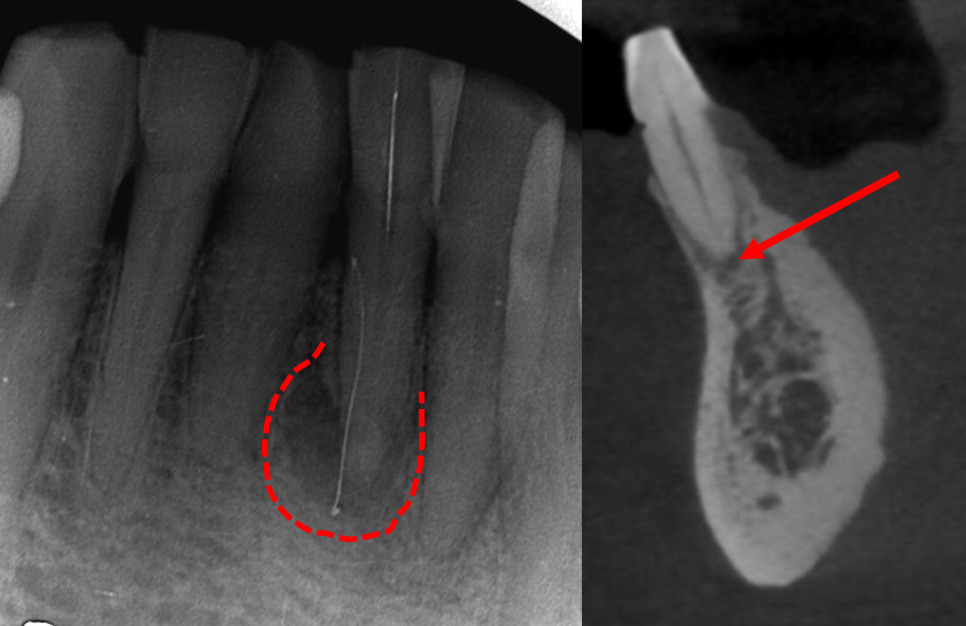

매탄동치과 바른본치과의원에서

촬영한 x-ray 사진입니다.

뿌리끝 뼈가 검정색으로 보이는 것으로 보아

뿌리끝 염증이 굉장히 심해 보입니다.

예전에 다치면서 치아내부 신경에 탈이 난것 같고

세월이 흐르면서 서서히 서서히

비가역성치수염을 넘어

치수괴사 상태까지 진행된 것으로 판단됩니다.

24.02.02(신경치료) – 69y 김OO님

매탄동치과로 앞니변색 및 앞니통증으로 내원한

환자분의 앞니 신경치료 중간에

치수의 염증이 너무 심해서

뿌리끝에서 올라오는 출혈이 심해

신경치료가 한번에 끝나지는 못했습니다.

치아 내부에 지혈에 도움이 되는 약재도 넣고,

전기치료도 동반해서

지혈과 소독을 반복해야 합니다.

신경치료를 2회에 걸쳐 마무리를 하고,

앞니통증은 모두 사라졌고,

환자분도 굉장히 편안한 상태에서

진료가 마무리 되었습니다.